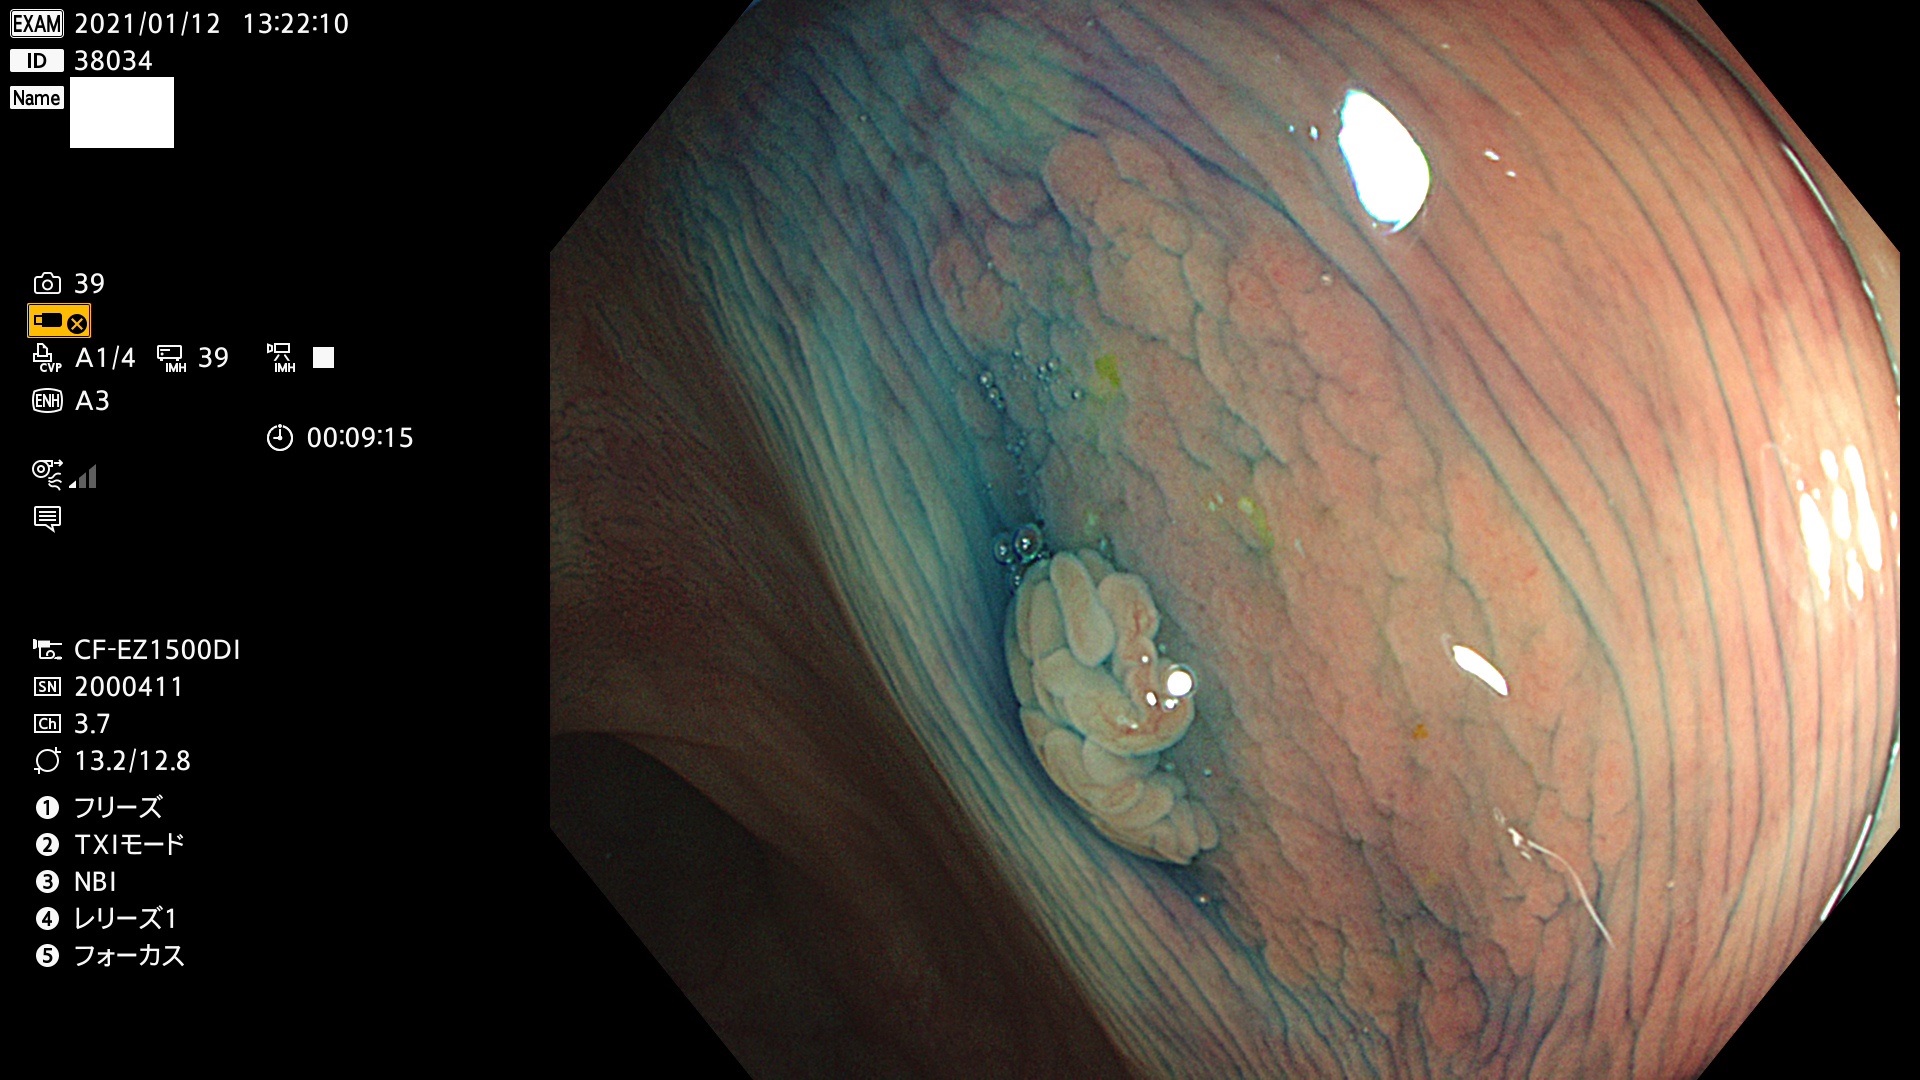

38001 38002 38003 38004 38006(SSAPのみ) 38007 38008 38009 38010 38012 38013 38014 38016 38018 38020 38021 38025 38026 38029 38032 38033 38034 38035 38036 38037(SSAPのみ) 38039 38043 38044 38048 38049 38050 38052 38055 38056 38057 38058 38059 38064(SSAPのみ) 38065 38068 38069 38070 38071 38072 38074 38075 38076 38078 38079 38080 38082 38083 38084 38085(SSAPのみ) 38086 38087 38088 38089 38090 38091 38092 38093 38094 38097 38098 38099

発見困難で危険性の高い平坦型病変(上記100名より抽出)